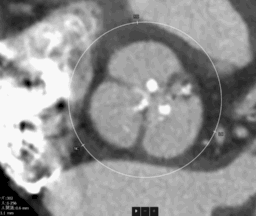

入院超声提示左室壁增厚,主动脉瓣回声增强,提示主动脉根部严重钙化。

CT报告示主动脉瓣钙化明显,左右冠散在钙化斑块。

CT数据显示该患者为三叶式主动脉瓣。

1. 主动脉瓣瓣环周长77.0mm,平均周长径24.5mm,SOV:32.6mm*351.4mm*32.2mm,瓣叶增厚,瓣上钙化明显,HU850钙化积分913mm³。